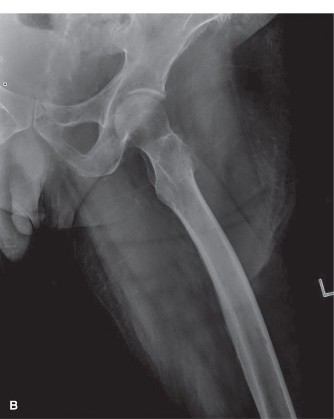

Initial plain radiographs of the left hip were obtained upon presentation. The anteroposterior (AP) and lateral views of the left hip demonstrated a comminuted, subtrochanteric fracture of the left femur. The fracture pattern involved significant cortical destruction and a large lytic lesion extending proximally into the intertrochanteric region and distally into the subtrochanteric area. The margins of the lytic lesion appeared ill-defined in several areas, raising strong suspicion for a neoplastic process. There was no evidence of periosteal reaction or overt sclerotic changes commonly associated with benign lesions or healing fractures.